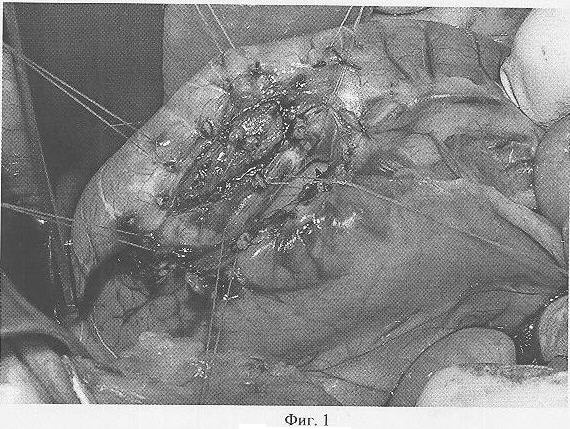

Способ осуществляется следующим образом. В положении собаки лежа на спине, на операционном столе под наркозом выполняют лапаротомию. На заданном участке стенки желудка или двенадцатиперстной кишки производят рассечение серозно-мышечной оболочки стенки кишки в форме овала или окружности диаметром более 20 мм. Отдельными узловыми швами прошивают видимые подслизистые сосуды по линии рассечения серозно-мышечной оболочки (фиг.1: формирование гигантской язвы двенадцатиперстной кишки с пенетрацией в поджелудочную железу у беспородной собаки). Иссекают участок стенки кишки между наложенными узловыми швами. Образованный дефект в стенке кишки фиксируют двухрядными швами по окружности к прилежащему органу (поджелудочной железе, печени, большому либо малому сальнику, соседней кишке, забрюшинному пространству и пр.). Ушивают брюшную полость.